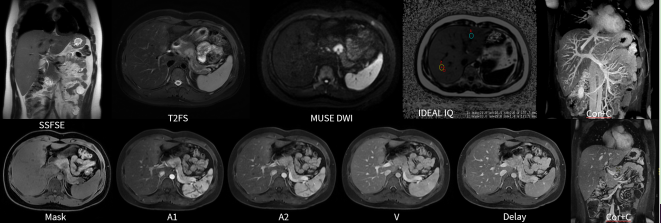

★图像质量高清!实现精准临床科研成像,高清的图像质量,可实现微小病灶的精细显示与分析,让病灶无处遁形,尤其在肿瘤和损伤的诊断方面独具优势。

★应用范围更广!能够完成包括神经系统、胸部、腹部、盆腔、心血管、骨骼关节、软组织、乳腺等全身各部位磁共振检查。